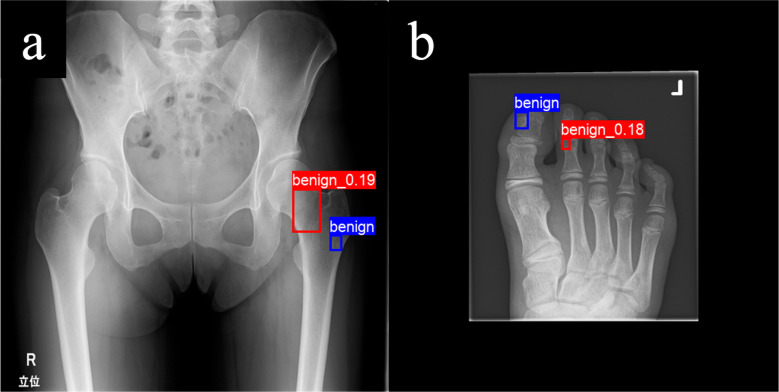

Results: The DINO model achieved a higher mean tumour detection rate (85.7% (95% CI 81.5 to 89.8)) than the YOLO model (80.1% (95% CI 77.2 to 82.9)). For the evaluation of classification performance, we used 113 cases that DINO detected out of 128 randomly selected cases as the evaluation test set. The accuracy and sensitivity of the DINO model, as a superior model, were significantly higher than those of general orthopaedic surgeons. The DINO model correctly classified 78.6% (22 out of 28 cases) of the challenging cases that two or more doctors misclassified. However, DINO's diagnostic errors primarily occurred with tumours that were diagnostically challenging for orthopaedic oncologists or present in unusual sites.